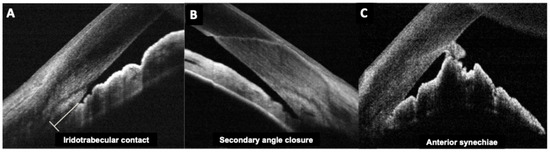

Background and Objectives: Optic disc drusen (ODD) can mimic papilledema and are linked to structural crowding, microvascular change, and visual-field loss. We synthesized structural/microvascular differences, functional status and change, diagnostic...